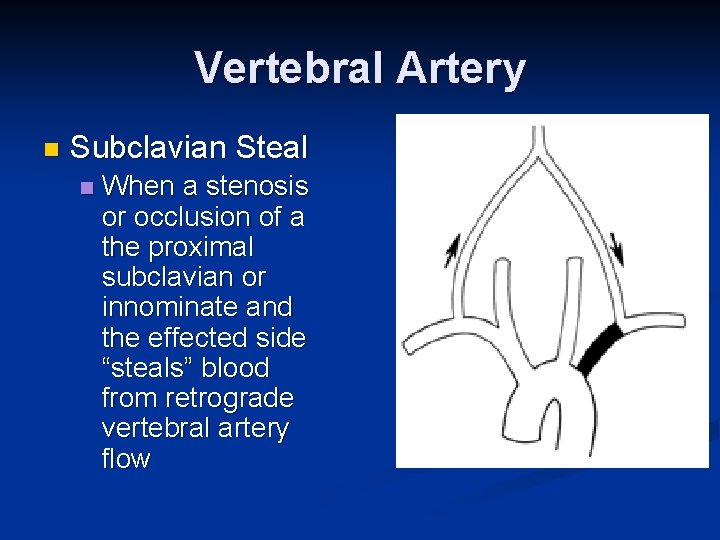

Vertebral Artery n Subclavian Steal n When a stenosis or occlusion of a the proximal subclavian or innominate and the effected side “steals” blood from retrograde vertebral artery flow

Distinguishing characteristics of the vertebral artery: n First branch off subclavian n Enters foraminal canal at C 6 n Asymmetrical size: left > right n Low resistance flow